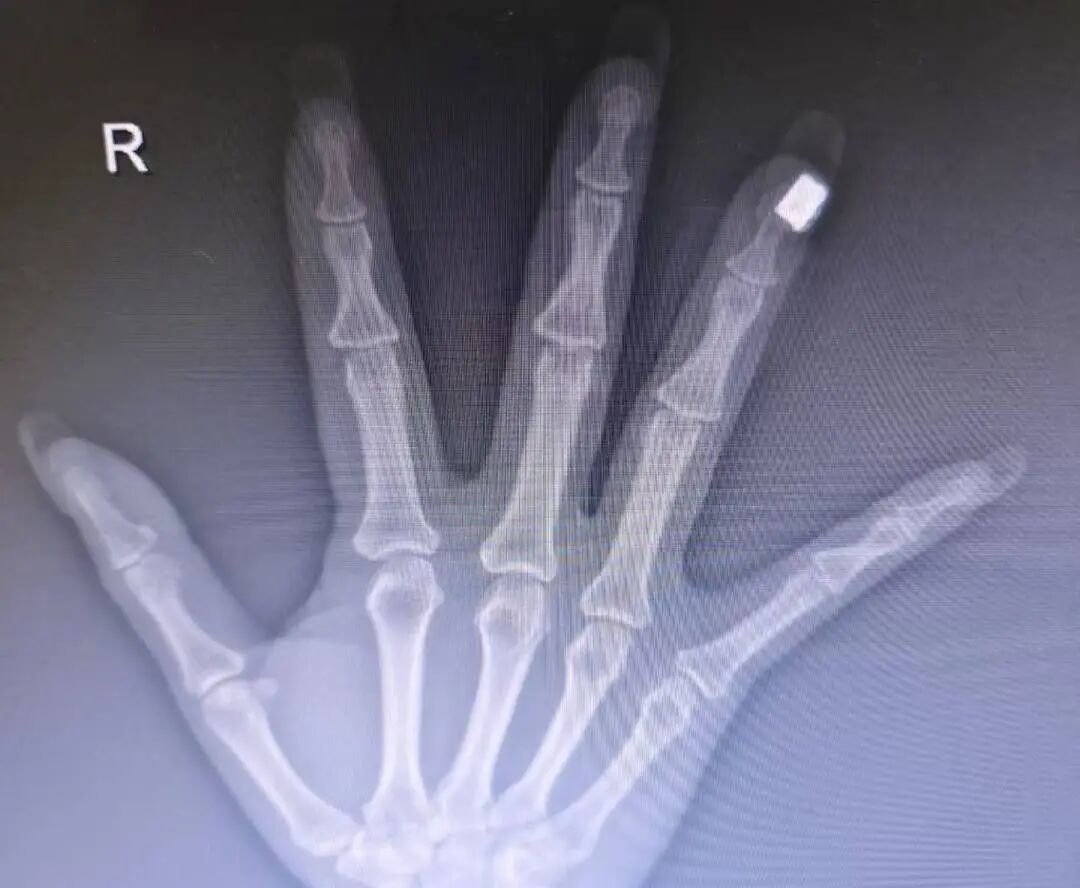

“有一次我在急诊接诊一位手外伤患者,给她拍手部X光时,意外发现美甲区域出现了高密度影,这说明美甲里面含有金属成分。”医生仔细观察后发现,患者的美甲上装饰有珠子或类似钻石的点缀,“外表看起来像是塑料或人造钻,但内核应该含有金属成分。”

该医生此前遇到的案例

他表示,核磁共振检查严禁携带任何金属物品。如果美甲饰品中含有铁磁性金属,在强磁场下可能被吸走,不仅可能伤及患者手指,还可能损坏昂贵的医疗设备。“问题是,很多做美甲的人可能并不清楚自己指甲上的装饰品是否含金属成分。”